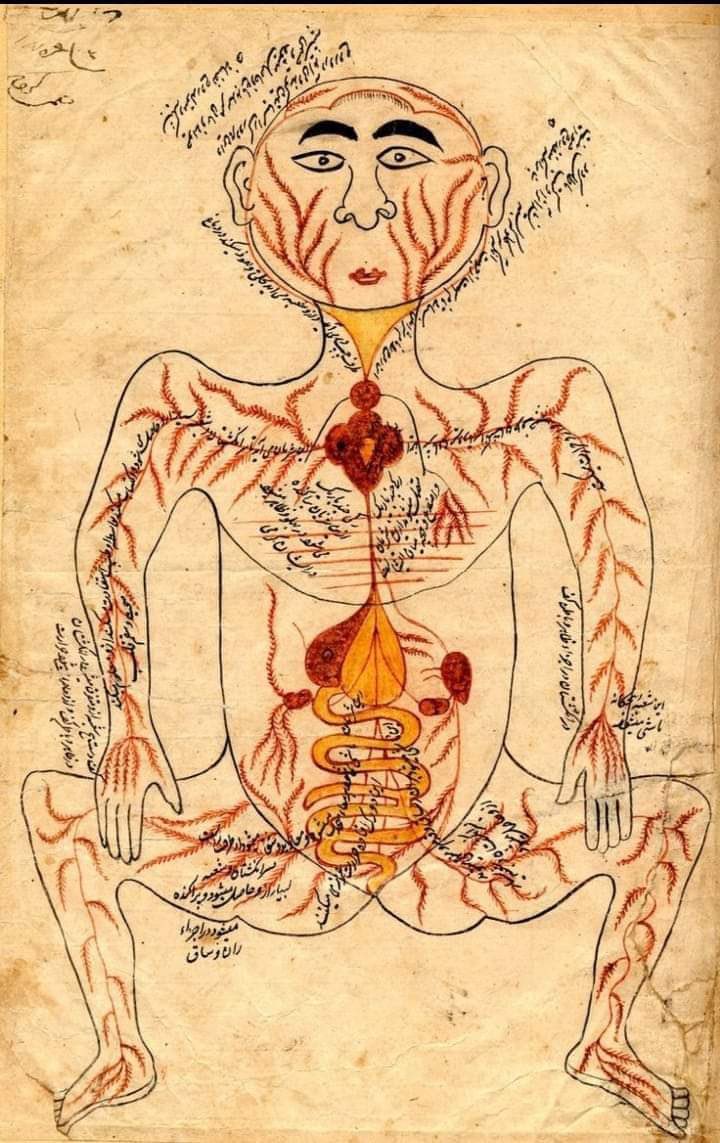

هذه الصورة التي أمامك تعود لعصر الطبيب إبن سينا ...

شاهد موضع القلب هنا ؟

تم رسمه فى المنتصف وليس جهة اليسار الحقيقة وبالرغم من بدائية الرسم إلا أن مكان القلب صحيح تمامًا .

لذلك معلومة أن القلب فى جهة اليسار هي معلومة خاطئة والتصحيح هو أن القلب البشرى يقع فى المنتصف خلف عظمة القص مع بعض الميل جهة اليسار عند معظم الأشخاص وليس جميعهم.

هذه الصورة التي أمامك تعود لعصر الطبيب إبن سينا ...

شاهد موضع القلب هنا ؟

تم رسمه فى المنتصف وليس جهة اليسار الحقيقة وبالرغم من بدائية الرسم إلا أن مكان القلب صحيح تمامًا .

لذلك معلومة أن القلب فى جهة اليسار هي معلومة خاطئة والتصحيح هو أن القلب البشرى يقع فى المنتصف خلف عظمة القص مع بعض الميل جهة اليسار عند معظم الأشخاص وليس جميعهم.